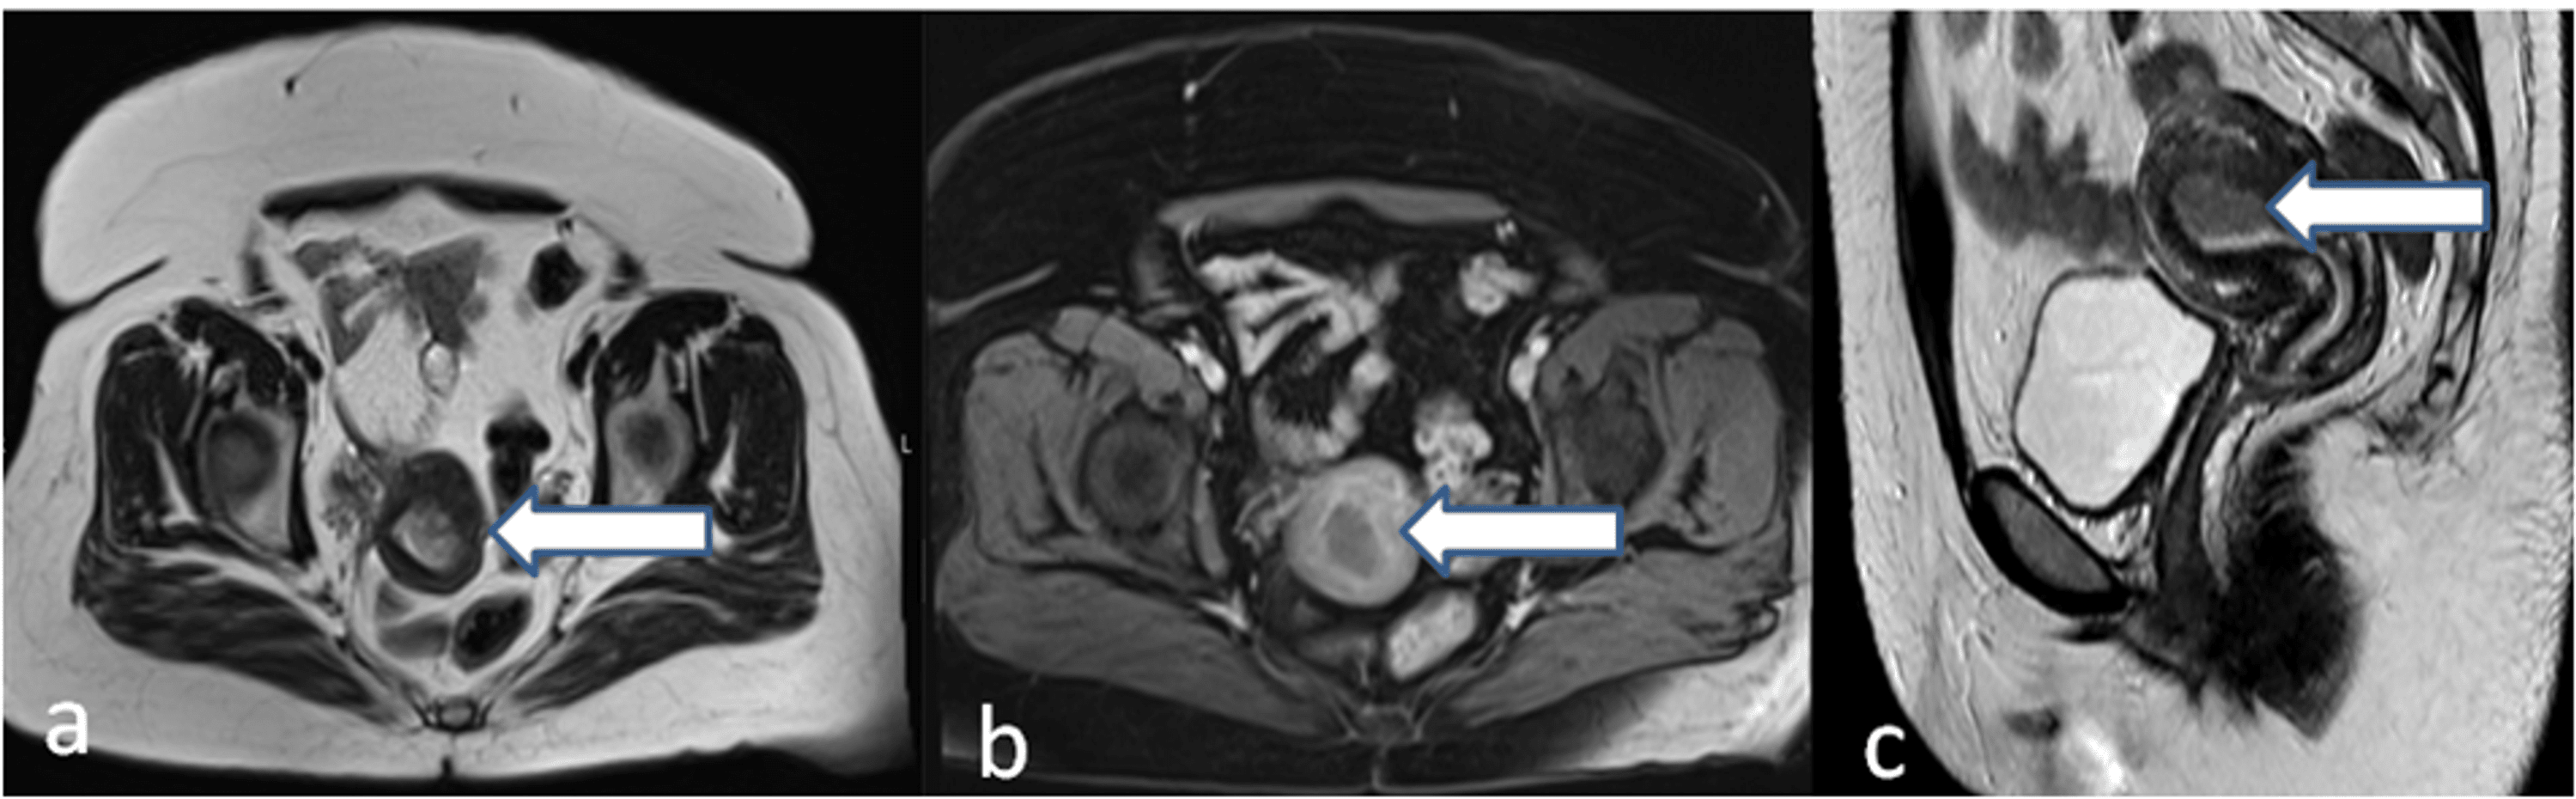

MRI in a 29yearold patient with abovecutoff (11.5 mm) endometrial Endometrial Measurement Mri mr reporting checklist for endometrial cancer staging. T2 hyperintense layer with a normal thickness corresponding to the present phase of the menstrual cycle, as with. the normal endometrium has a wide spectrum of appearances according to the patient’s age and phase of. endometrial thickness is well assessed on mri. mri plays a valuable role in evaluating. Endometrial Measurement Mri.